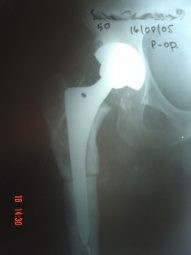

Prótesis Total de Cadera

Envíado por Dr. Ricardo Antonio Gómez G.